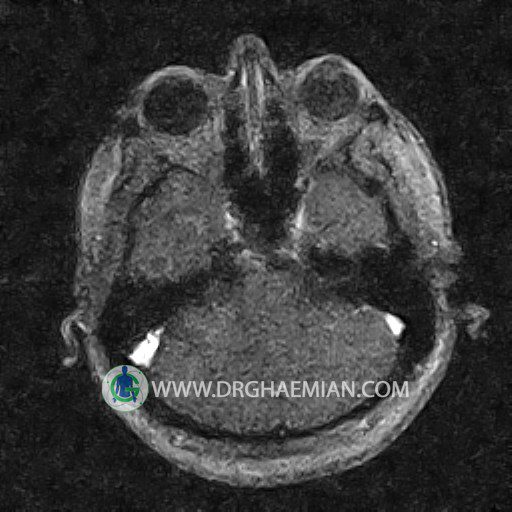

ام آر وی یک روش تصویربرداری دقیق و غیر تهاجمی است که برای معاینه ورید های بدن و ارزیابی سلامت رگ ها استفاده می شود. ورید ها خون را از اعضای بدن به قلب باز می گرداند تا دوباره اکسیژن و مواد مغذی به خون داده شود. ام آر وی جریان خون را ارزیابی و موارد غیرعادی مضر مانند لخته های خونی را شناسایی می کند. در این کیس ترومبوز دیواری مغز در سینوس عرضی راست و ترمبوز جزئی در سینوس عرضی چپ دیده می شود.

Images of the venous cranial vessels demonstrates a superior sagittal sinus of normal caliber with normal arrangement of draining superficial cerebral veins.

The great cerebral vein Galen inferior sagittal , straight sinus and left sigmoid sinus appear normal.

The right sigmoid sinus present a normal caliber.

The other evaluable deep cerebral veins , basal and labbe are normally developed and patent.

The other evaluable portions of the neurocranium show no abnormalities.

– Narrowing of left transverse sinus with filling defect & inthimal irregularity

suggestive for partial thrombosis

– Inthimal irregularity in anterior wall of right transverse sinus suggestive for mural thrombosis

are seen